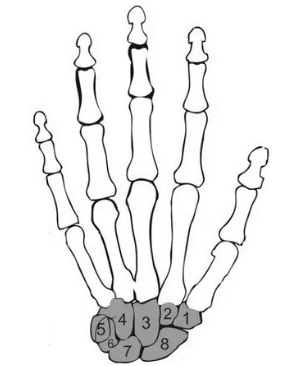

Os ossos da mão, juntamente com os músculos e articulações, permitem o manuseio de objetos. Os ossos em destaque das numerações do 1 ao 8, tratam-se dos ossos do carpo.

Os ossos chamados de Escafoide, Semilunar, Hamato e Capitato, estão dispostos em que numerações, respectivamente?